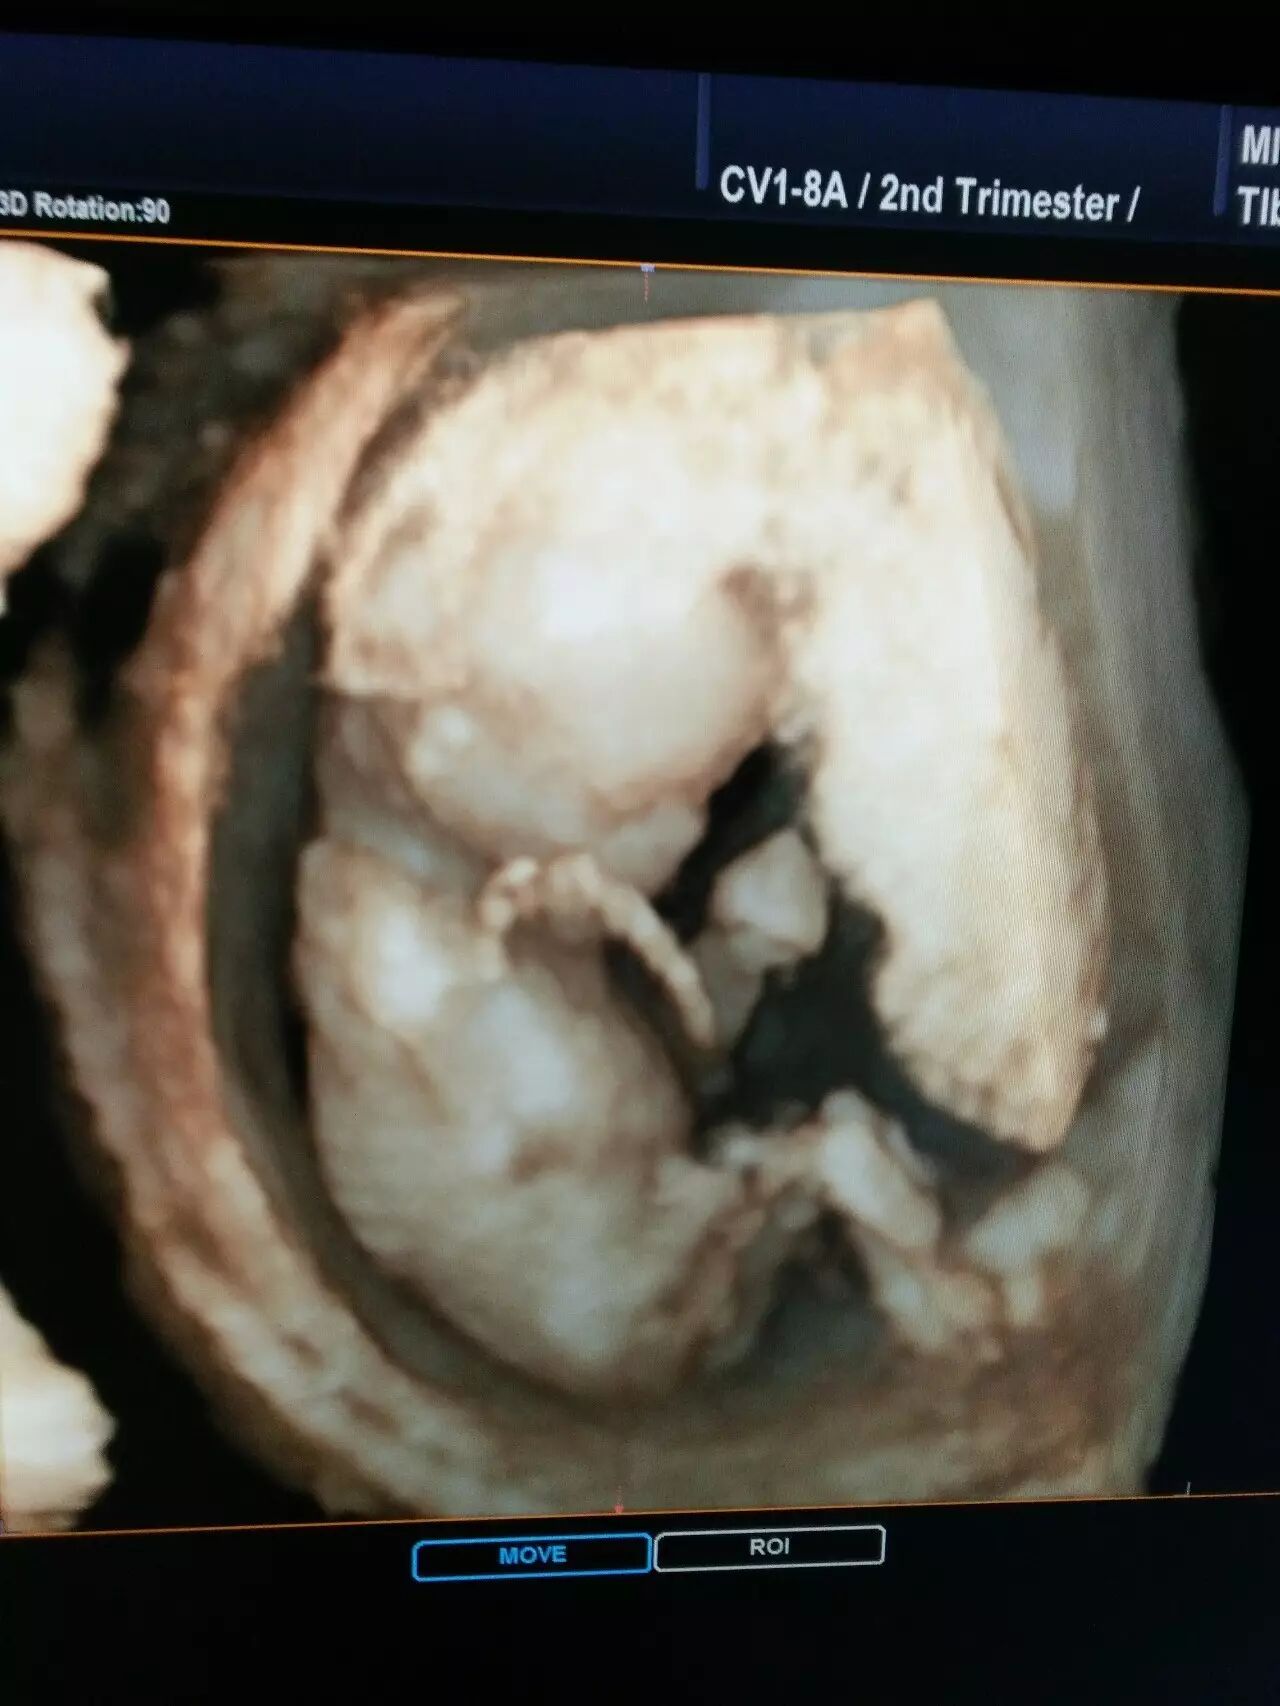

爸爸妈妈用仁德医院的超高端四维彩超

看到的我是酱紫的

(图片来自仁德医院彩超室)

★四维彩超:“4D”是“四维”的缩写,也被称作实时三维。对于超声学来说,4D超声技术是彩超行业的革命性突破。就像是摄像机所拍摄所拍摄到的画面。看到的是立体图像,能看到胎儿的上下左右前后的情况,能更加准确的看到胎儿的情况。

★超高端四维彩超:是采用4D超声图像加上空间维度参数,获取更加立体、逼真的四维图像,超越了传统灰阶超声的大部分限制。其结果是:能够栩栩如生的显示宝宝在妈妈肚子里的实时动态活动高仿真图像,精准排查胎儿畸形。